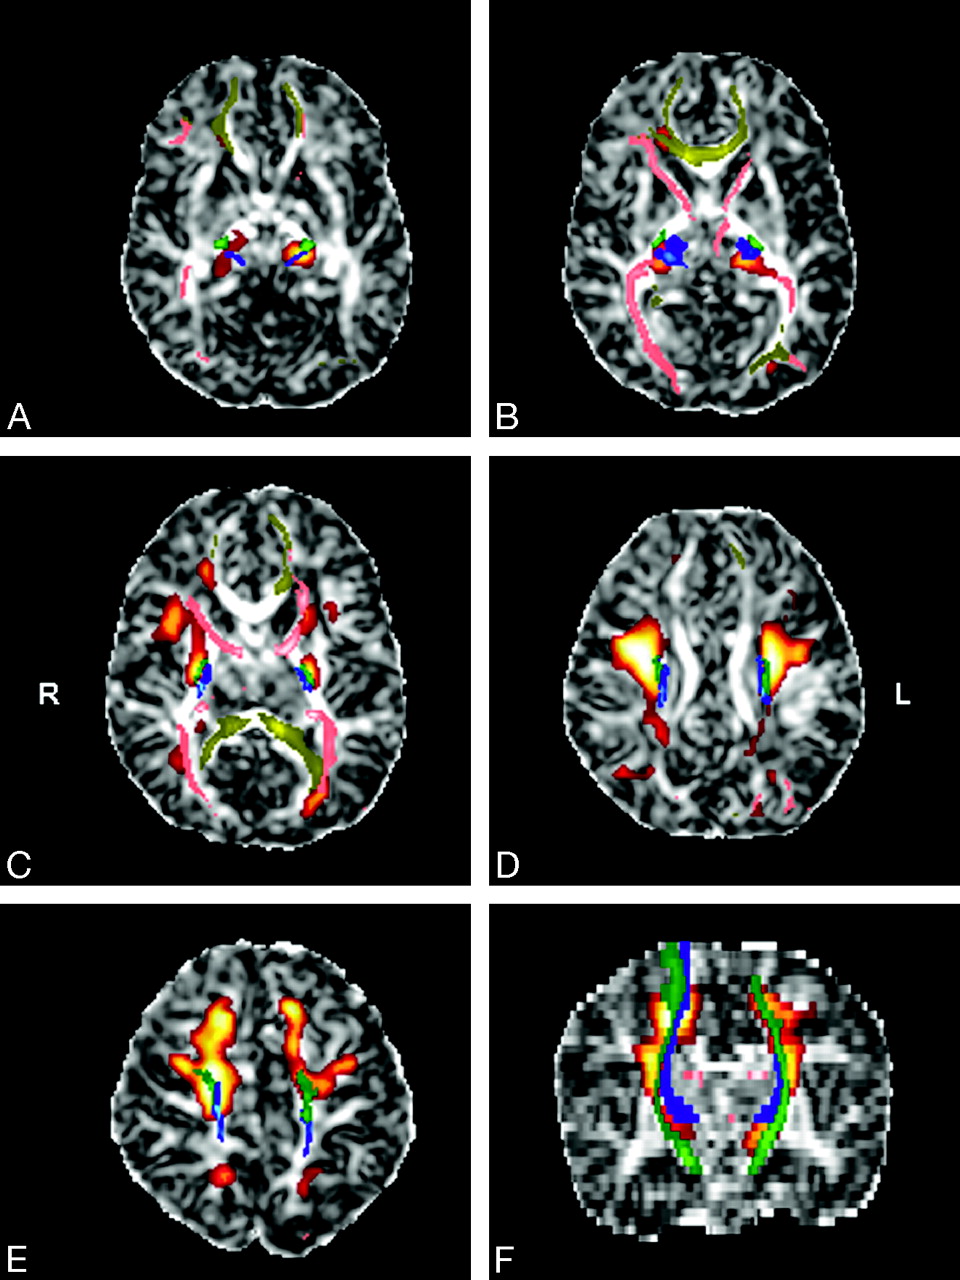

Areas with significant FA increase with age are located in the thalami (A, B), the anterior and posterior arms of the internal capsules, and the optic radiations (C), the centrum semiovale (D), and the subcortical projection pathways of the frontal and parietal cortices (E) in the axial (A–E) and coronal (F) planes. The anatomic underlay is the FA image of the template. The color maps represent the F-scores. Only regions of more than 50 voxels attaining a corrected P value of less than .05 for the voxel-level of statistical inference were considered significant.

Superimposition of statistical parametric maps (red-orange), probabilistic tractography images (blue, green, pink, yellow), and FA images of the template in the axial (A–E) and coronal (F) planes. The CST (green), the STR (blue), the ATR, the PTR (pink), and the CR (yellow) are included in the significant voxels of the parametric analysis.